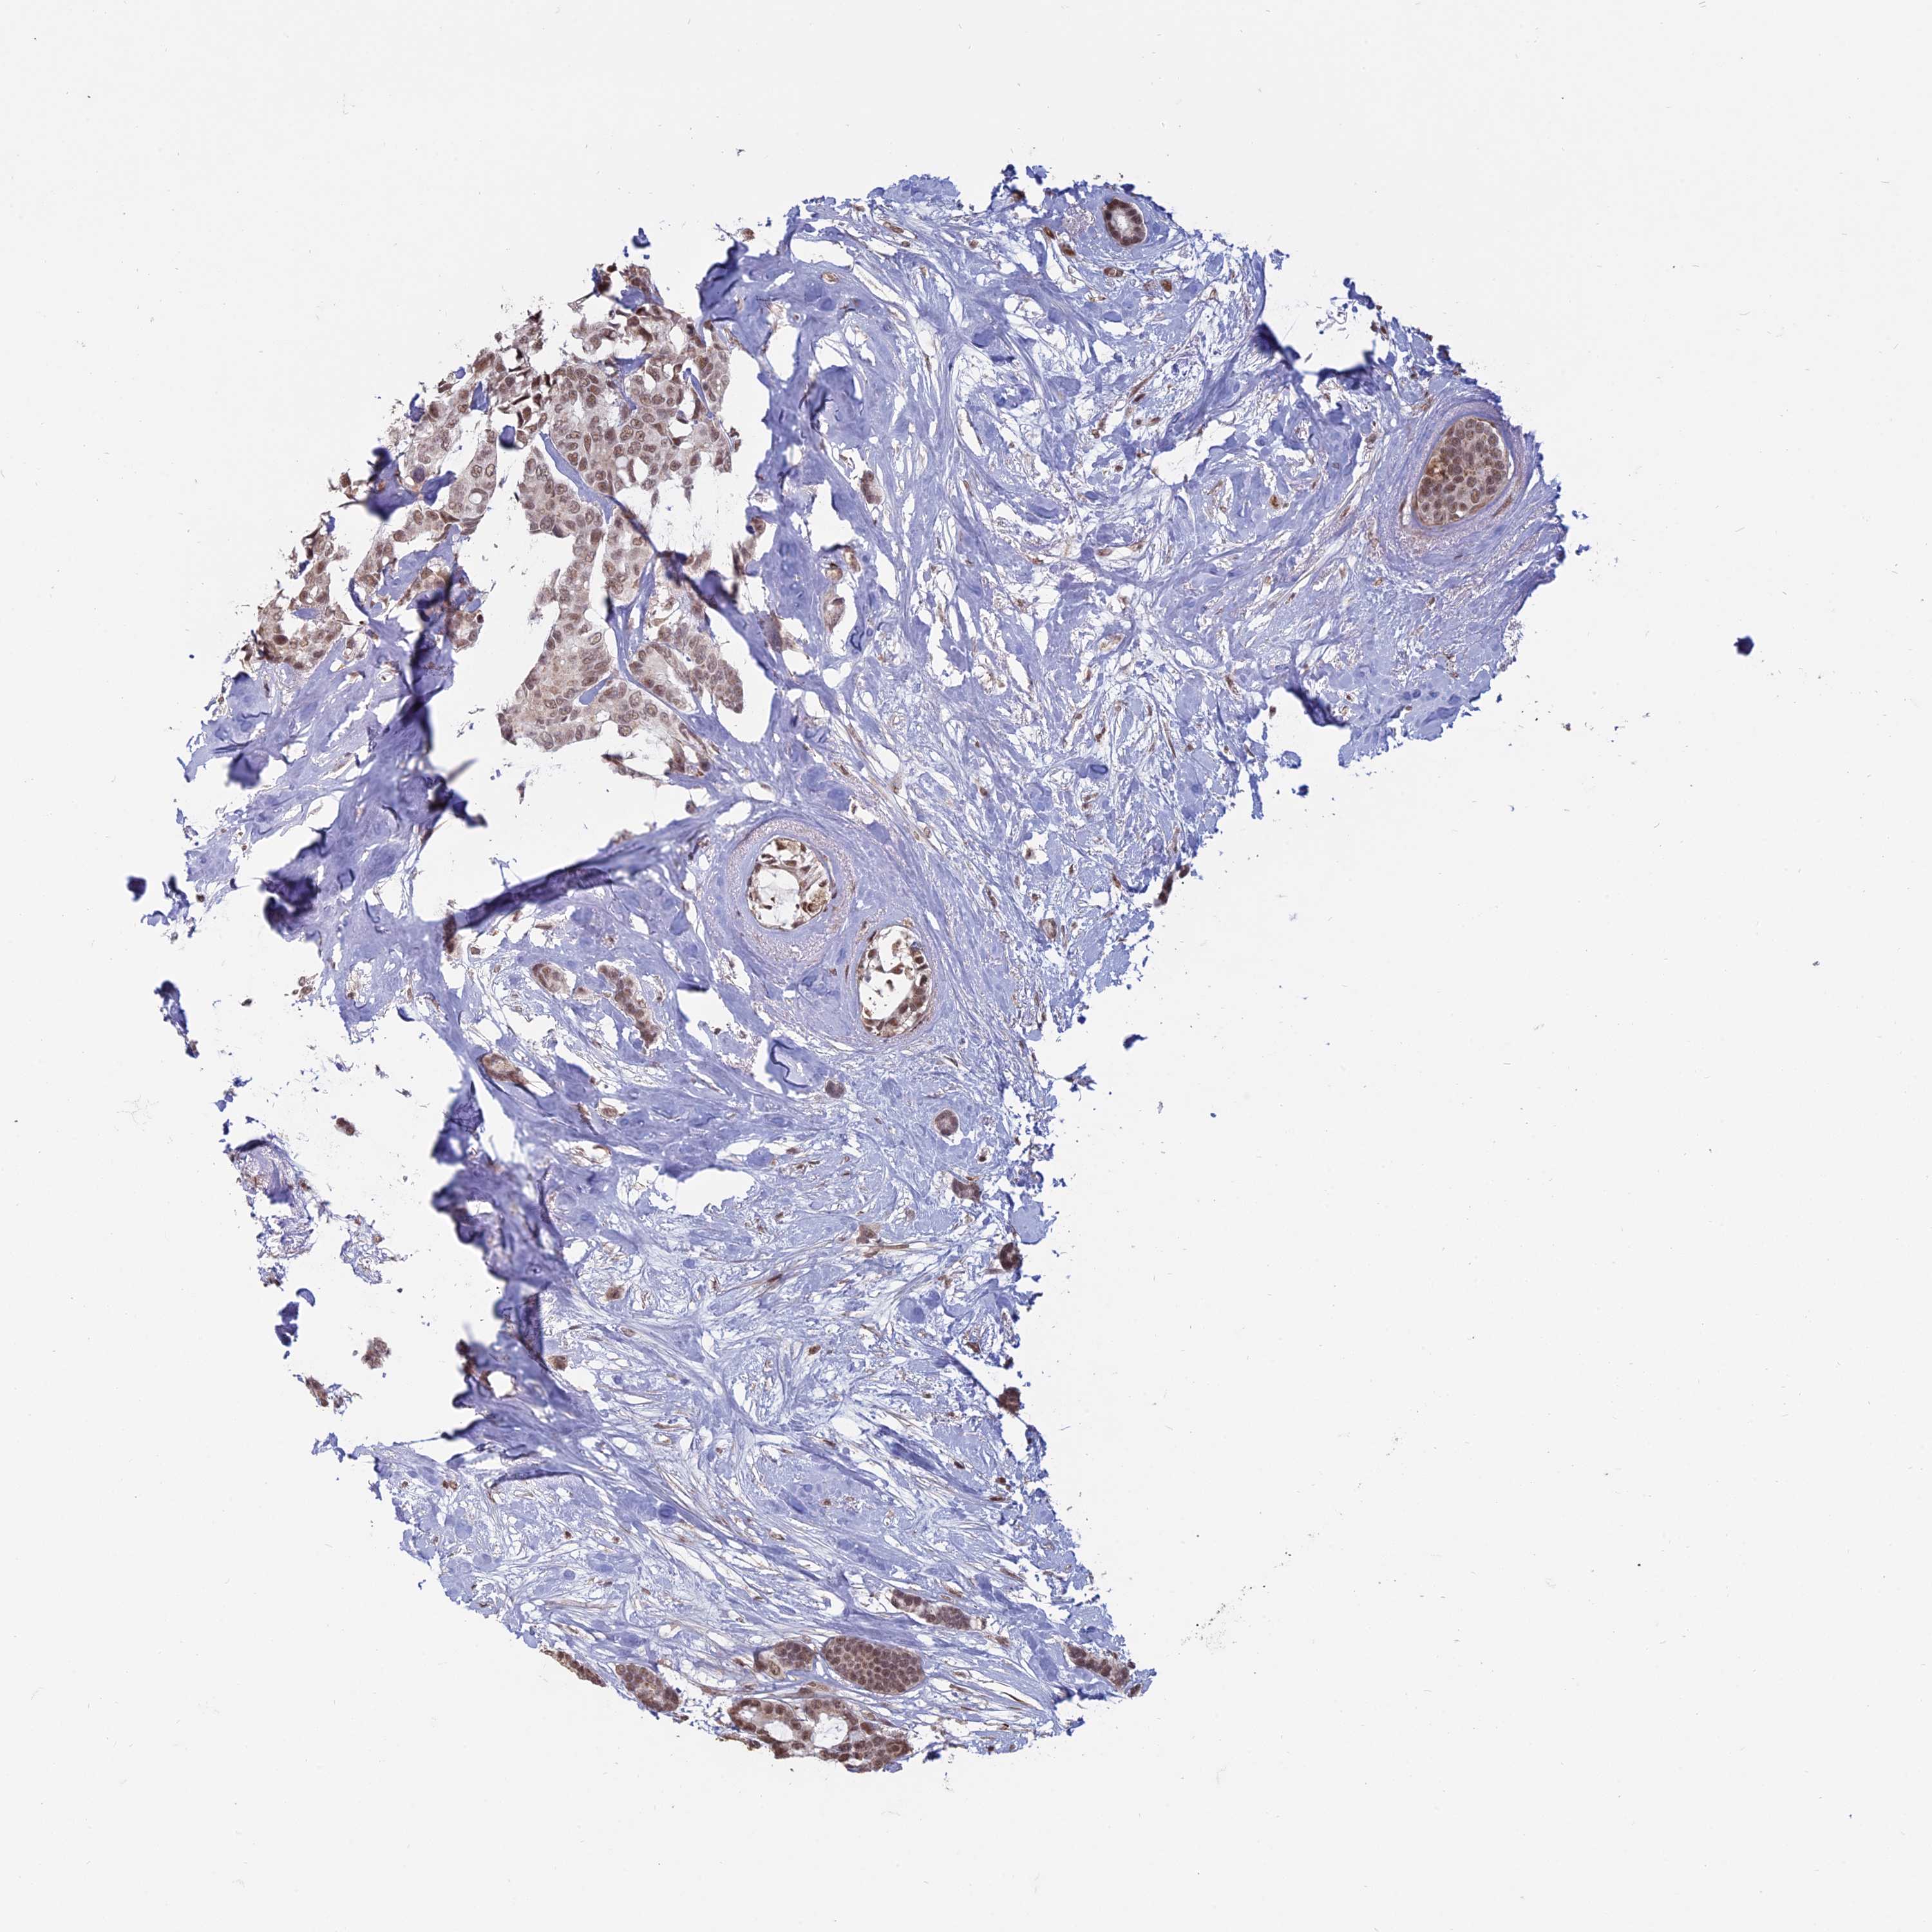

BRCA TCGA BRCA VALIDATION PROTEIN EXPRESSION

ANTIBODIES

AND

VALIDATION